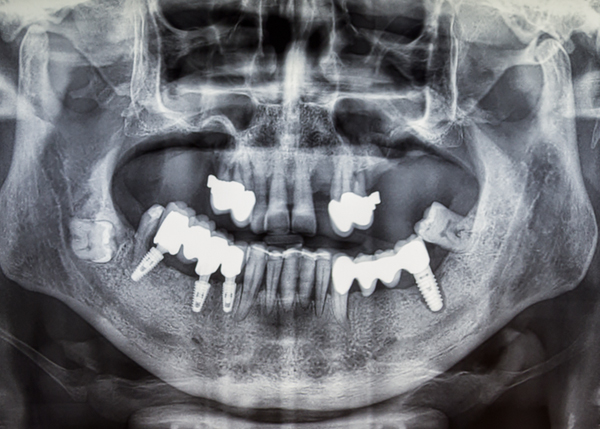

일반 임플란트

치아 상태 및 신경의 위치를 2D(평면)으로만 확인이 가능해

정확한 진단이 어려움